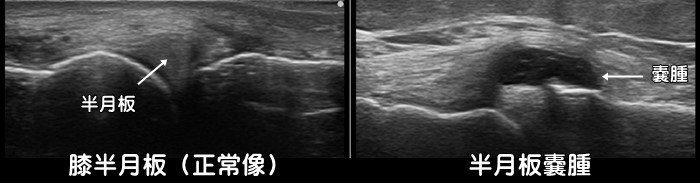

半月板嚢腫・メニスクスガングリオン

半月板が断裂しそれに伴って嚢腫と呼ばれる袋ができることがあります。主に加齢による水平断裂で発生しやすいと言われています。但しエコーでは半月板の損傷は一部を除き描出できません。膝が引っ掛かる(キャッチング)や膝が曲がったまま伸びなくなる(ロッキング)の症状があればMRI検査が必要です。

半月板亜脱臼

変形性膝関節症になると骨と骨との隙間が狭くなります。するとその間にあるクッションの半月板が外に押しやられるように飛び出します。これが半月板の亜脱臼です。座った状態では亜脱臼がなくても立った状態で膝に体重がかかると亜脱臼がみられる方もおられます。